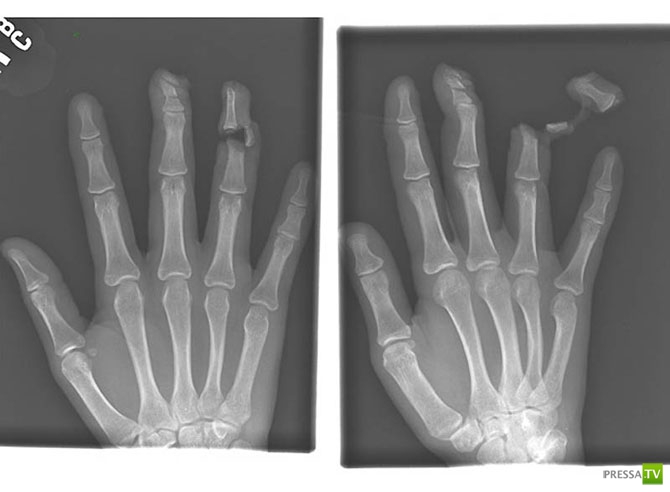

Гвоздь в костях указательного и среднего пальцев взрослого мужчины.